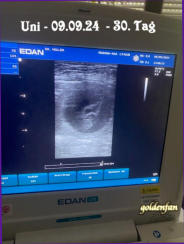

10.10. - 05.00 Uhr - eine sehr unruhige Nacht, sie mußte mehrfach raus, um ihren Darm und Blase zu leeren Temperatur ist noch nicht wieder auf normal 08.30 Uhr - die Vorblase ist geplatzt die den Geburtskanal weitet 09.38 Uhr - ein süßer Rüde (blau) 10.59 Uhr - ein süßer Rüde (lila) 12.31 Uhr - ein niedliches Mädchen (rot) 13.15 Uhr - ein süßer Rüde (schwarz) 13.45 Uhr - ein süßer Rüde (hellgrün) 15.44 Uhr - ein niedliches Mädchen (rosa) 18.09 Uhr - ein süßer Rüde (grau) 01.00 Uhr - ein kleines Mädchen das leider nur als Engel auf die Welt kam, wir konnten ihr nicht helfen 09.10. - 11.00 Uhr - die Temperatur ist leicht abgesunken - Futter hat aber noch geschmeckt, ich halte Euch auf dem Laufenden 17.00 Uhr - Temperatur gleichbleibend, Abendbrot wurde zwar genommen, aber so richtig Appetit hat sie nicht 21.00 Uhr - Temperatur ist langsam wieder ansteigend - Uni schläft zwischen unruhigen Phasen 08.10. - lange draußen bleiben mag sie nicht mehr, sobald sie ihr Geschäft gemacht hat, geht sie sofort zurück ins Haus - Temperatur konstant 07.10. - die Kleinen wären jetzt lebensfähig, aber noch ist alles ruhig, Unis Temperatur ist konstant 06.10. - 8 Wochen - neues Foto eingefügt - sie wiegt 43 kg bei einem Umfang von 102 cm 05.10. - wir kontrollieren täglich ihre Temperatur, die sehr konstant ist, also alles Ok. So wissen wir ihre Normaltemperatur und bemerken einen Abfall sofort, der ca. 24 Stunden vor der Geburt stattfinden wird, und erst wenn die Temperatur wieder auf normal angestiegen ist, geht es bald los. 04.10. - unsere nächtlichen Gartenrunden sind nun schon auf 2-3 mal gestiegen, die Kleinen drücken schon arg auf ihre Blase 03.10. - unter strenger Aufsicht haben wir die Wurfkiste gebaut und alles fertig gemacht, Uni und Familie waren mit uns zufrieden 02.10. - Futtern geht nun auch schon langsamer, aber der Napf wird blitzeblank geleert 01.10. - so langsam wird alles mit dem Welpenbauch beschwerlich, aber trotzdem ist sie noch sehr agil und marschiert munter herum 30.09. - die Bewegungen der Kleinen zu spüren ist ein wundervolles Gefühl, doch Uni gefällt es nicht, wenn man die Hand ruhig auf ihren Bauch legt, sie will lieber gestreichelt werden 29.09. - 7 Wochen - aktuelles Foto eingefügt, ihr Gewicht 41,5 kg bei einem Umfang von 98 cm 28.09. - eine gemütliche Schlafposition zu finden ist nun schon gar nicht mehr so leicht 27.09. - bei unserer nächtlichen Runde haben wir einen Igel getroffen, das fand Uni super interessant 26.09. - ihr Futter wird nun auf 3 gleiche Portionen verteilt, damit die Menge nicht zu doll auf den Magen drückt 25.09. - ihr Umfang beträgt nun 96 cm, das Gesäuge bildet sich auch schon 24.09. - sie ist etwas kurzatmig, aber davon ist sie völlig unbeeindruckt 23.09. - Uni geht es super, Futter schmeckt und ist wie immer viel zu wenig 22.09. - 6 Wochen - aktuelles Gewicht 39,5 kg bei einem Umfang von 94 cm 21.09. - Uni döst viel mehr als normal, doch sobald wir aufstehen, steht sie hinter uns, es könnte doch was zu futtern geben 20.09. - sie hat die Angewohnheit sich immer dahin zu legen, wo es sowieso eng ist 19.09. - ihr kleines Bäuchlein kann sie nun schon nicht mehr in ihrem Fell verstecken 18.09 - auf frisch gemähten Gras sich zu wälzen findet sie toll, trotz Umfangs von nun schon 91 cm 17.09. - Uni geht es prima, ihr Napf wird blitzeblank geleert, so dass ja nicht ein Mikrokrümel noch drin ist 16.09. - das Liegen auf dem Sessel ist nicht mehr so bequem, das stört das Bäuchlein 15.09. - 5 Wochen - neues Foto eingefügt, aktuelles Gewicht 37 kg - Umfang 89 cm 14.09 - nachts braucht sie schon eine Gartenrunde, da ein Kleines direkt auf ihrer Blase liegt 13.09. - sie bekommt nun Welpenfutter, das schmeckte ihr sehr gut 12.09. - so langsam verschwindet ihre Taille - Umfang 87 cm 11.09. - ihre Lieblingsbeschäftigung ist das genüßliche Kauen von Kaffeebaumhölzern mmh die sind echt lecker 10.09. - beim Füttern schaut sie mich jedes Mal an - ist das Dein Ernst - sooo wenig - ihr geht es super 09.09. - an ihrem Geburtstag wurde ihre Trächtigkeit durch Ultraschall bestätigt - siehe Foto 08.09. - 4 Wochen - aktuelles Foto eingefügt, Gewicht 36 kg - Umfang 84 cm - Morgen Ultraschalltermin 02.09. - der Ultraschalltermin ist am 09.09.24 um 15. 00 Uhr - das ist ihr 30. Tag - mal schauen ob Uni sich selbst auch ein Geburtstagsgeschenk machen wird? 01.09.- 3 Wochen - es geht Uni prima - aktuelles Gewicht 36 kg - Umfang 82 cm - neues Foto eingefügt Morgen werden wir einen Ultraschalltermin beim Tierarzt festlegen 25.08.- 2 Wochen - Uni versucht sich immer abseits der Schmusebande zu legen um ihre Ruhe zu haben - aktuelles Gewicht 36,5 kg -Umfang 81 cm - neues Foto eingefügt 18.08.- eine Woche ist nun schon vergangen, Uni ist schon sehr ruhig, aber das kann auch durch die Hitze sein - ihr aktuelles Gewicht 37 kg (bisschen viel aber Diät geht na klar nun erstmal nicht) Umfang 76 cm Sie bekommt nun eine spezielle Kräutermischung, die ihr sehr gut schmeckt - neues Foto eingefügt 12.08. - auch heute haben die beiden Hochzeit gefeiert 11.08. - heute hat sich Uni für Aragog entschieden (er ist der Vater von Jupiter), er gefiel ihr sofort und sie haben Hochzeit gefeiert 09.08. - Heute haben Uni und Jupiter sich kennengelernt, sie mögen sich sehr gern, doch für eine Verpaarung war es noch etwas zu früh 31.07. - Uni ist läufig